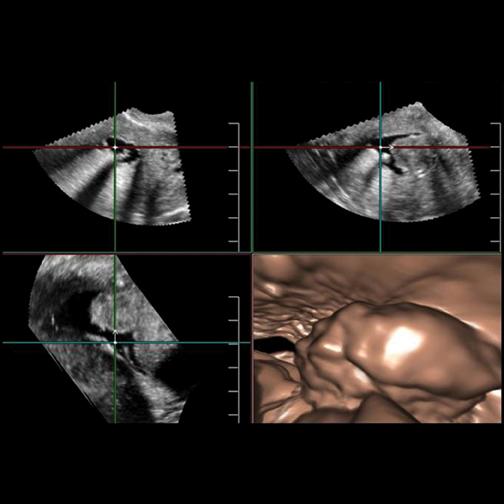

Despite decades of progress in breast imaging, one challenge continues to test even the most skilled radiologists ...

For patients with advanced breast cancer, positron emission tomography (PET) and magnetic resonance (MR) imaging can improve quality of life and survival by providing physicians with information on the effectiveness of chemotherapy prior to surgery, say researchers presenting at the 2013 Annual Meeting of the Society of Nuclear Medicine and Molecular Imaging.